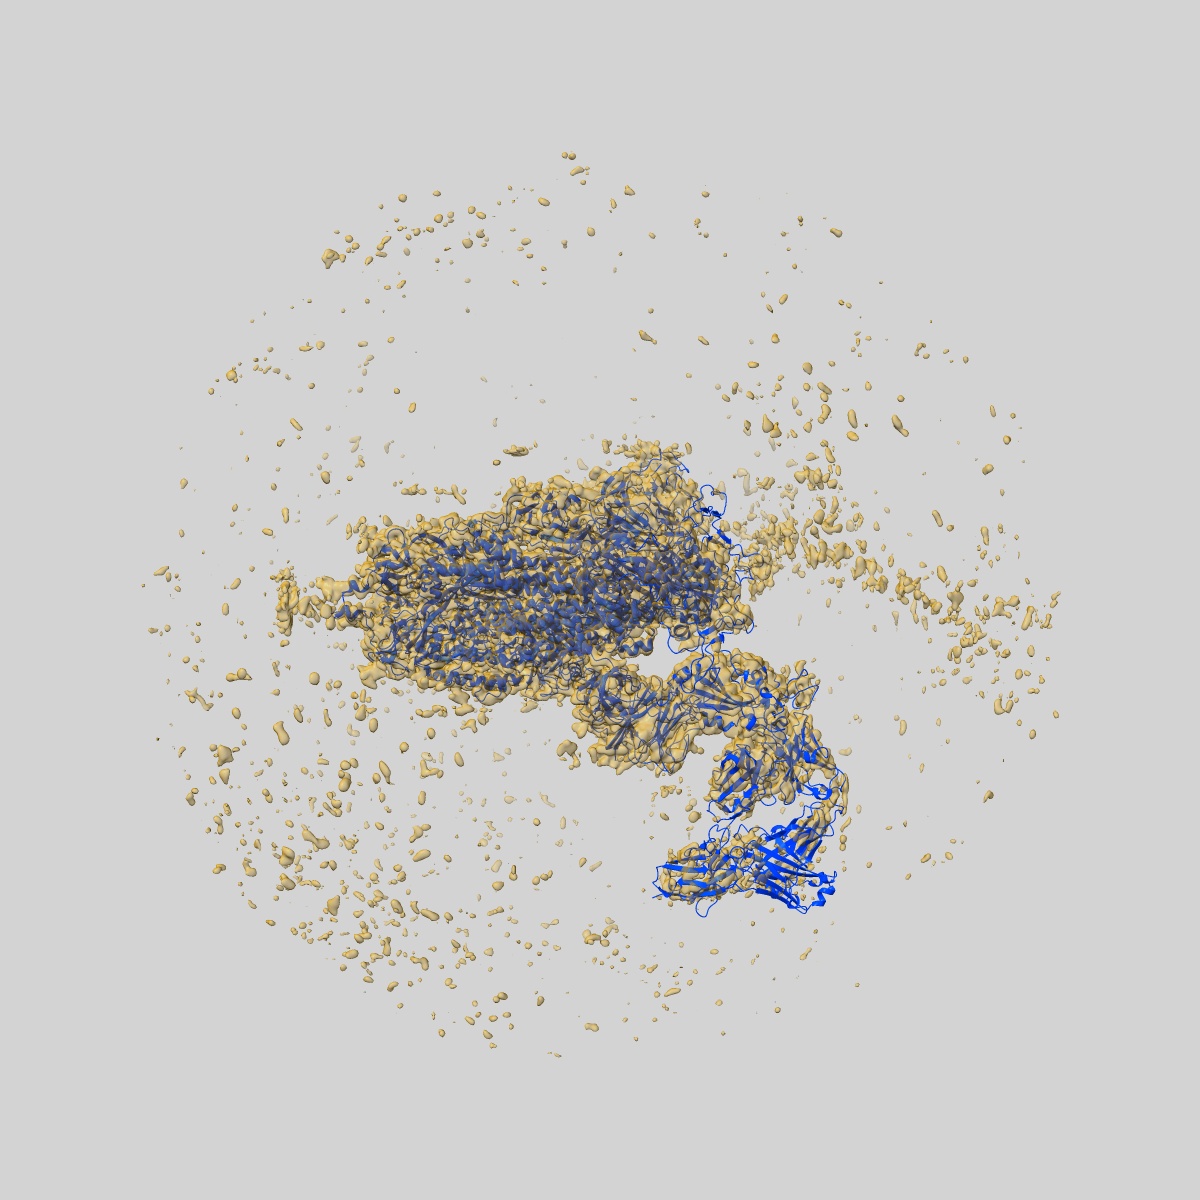

EMD-32683

SARS-CoV-2 Omicron Variant S Trimer complexed with one JMB2002 Fab

Single-particle3.18 Å

Sample: SARS-CoV-2 Omicron Variant S Trimer complexed with JMB2002 Fab

Fitted models: 7wpd

Structures of the Omicron spike trimer with ACE2 and an anti-Omicron antibody.